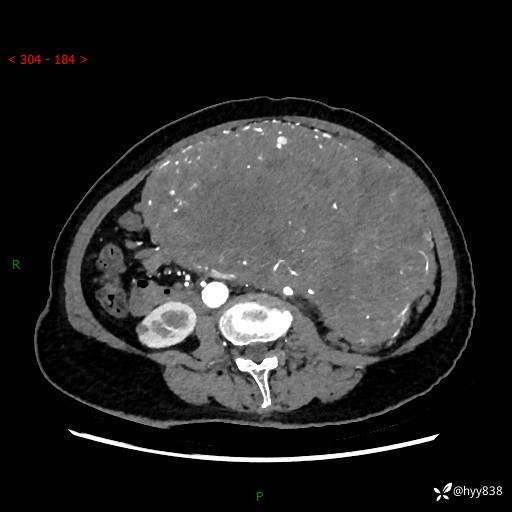

据说只有腹膜后,才能见到如此巨大的肿块---(有结果)

主诉:发现腹膜后占位1周

简要病史:患者1周前因头晕在当地第二人民医院检查发现左侧腹膜后区巨大富血供占位性病变,患者自诉腹部稍硬,无其他不适,无血尿,无腰痛等不适,患者为求进一步治疗来我院,门诊以“腹膜后占位性病变”收入我科。 起病以来,患者精神、饮食、睡眠可,大便正常,小便如上述,体力体重无明显改变。

临床诊断:腹膜后占位

腹部CT增强(动脉期+静脉期 ) ---平扫外院